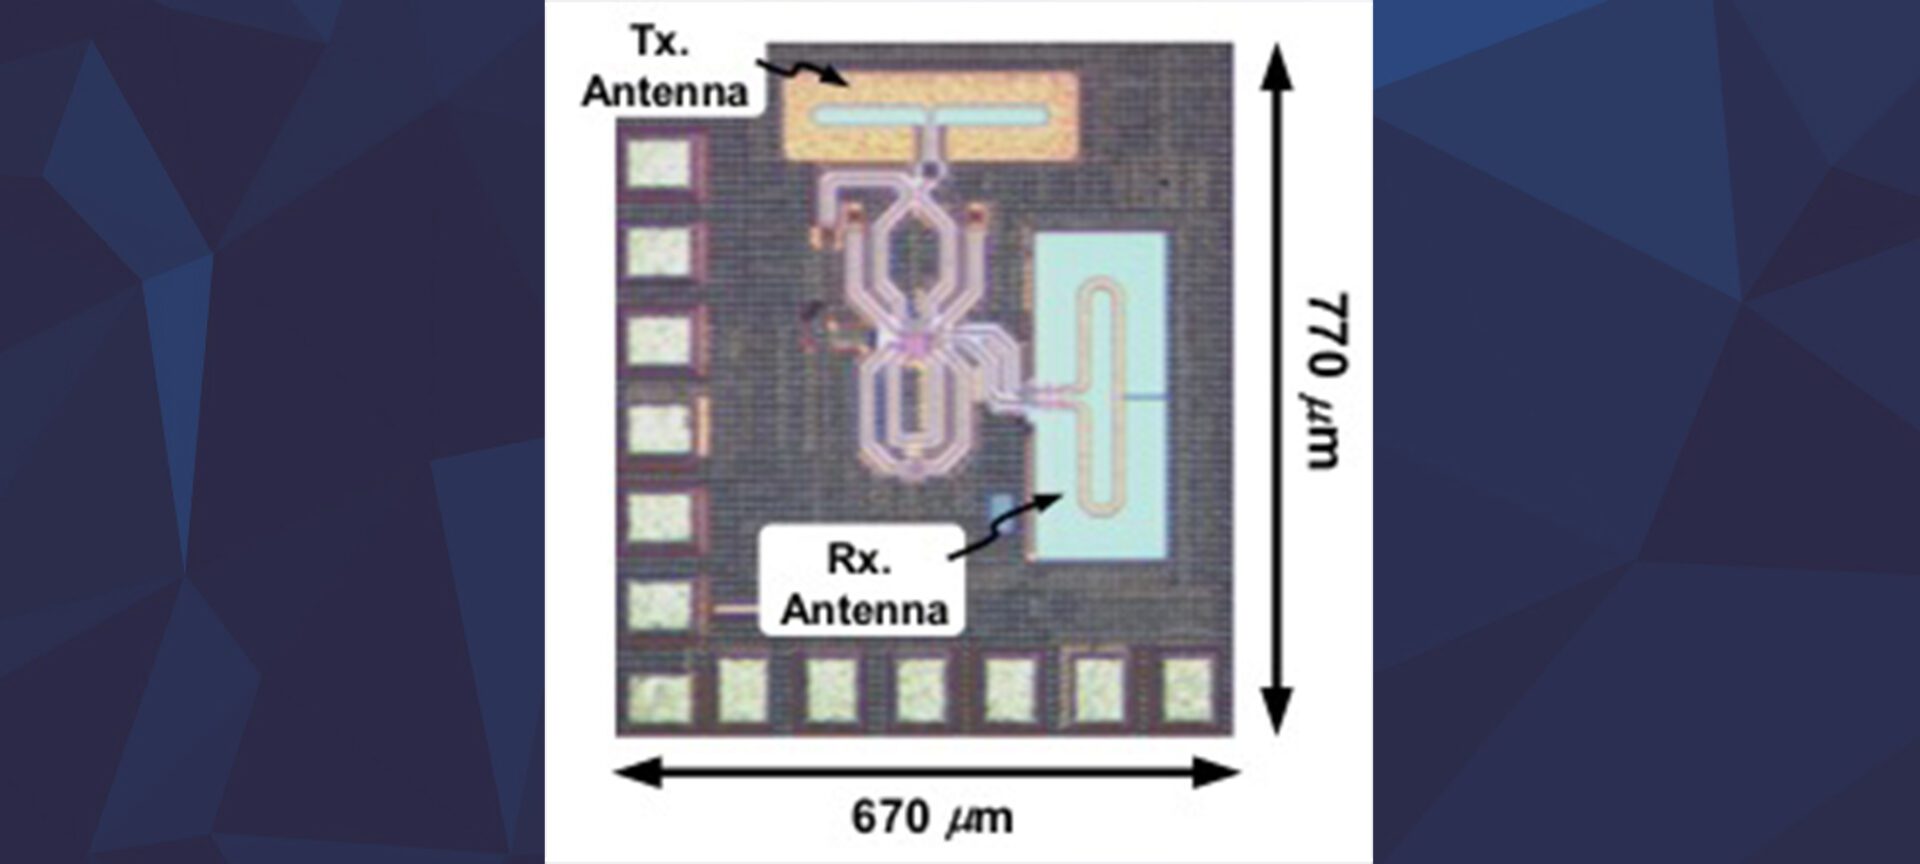

Afshari group receives Best Invited Paper award at the 2019 IEEE Custom Integrated Circuits Conference

Terahertz and sub-terahertz imaging can provide superior results in some biomedical imaging, spectroscopy, and water saturation detection.